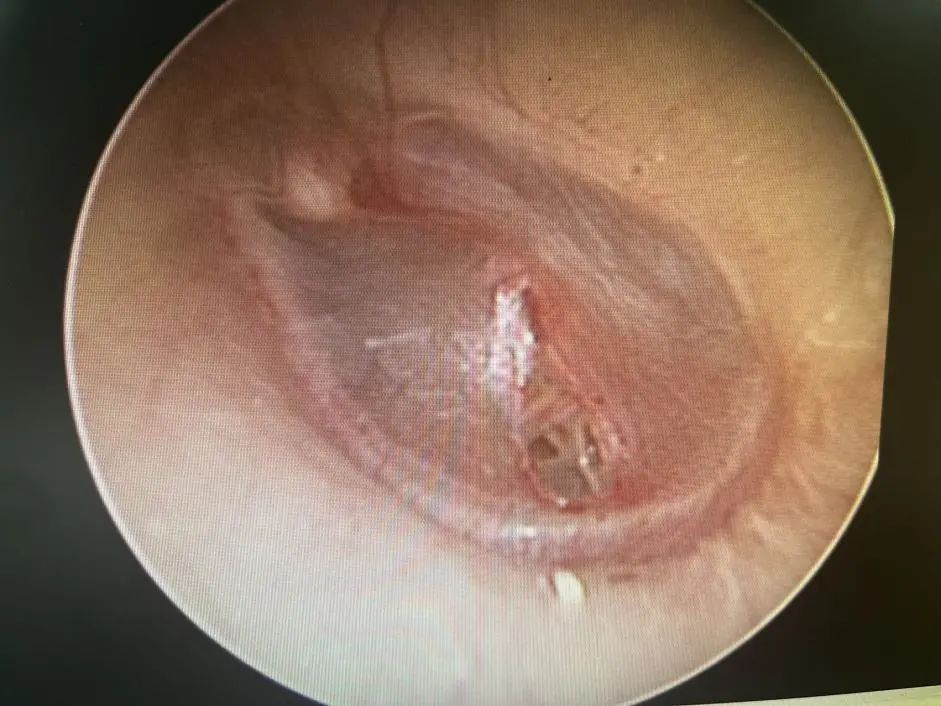

醫(yī)生在視頻耳內(nèi)鏡下發(fā)現(xiàn)左側(cè)鼓膜有一個破口,有血跡殘留在鼓膜上,還做了純音聽閾檢測,檢查結(jié)果顯示,小花的左耳聽力呈中度傳導(dǎo)性耳聾。

鼓膜穿孔